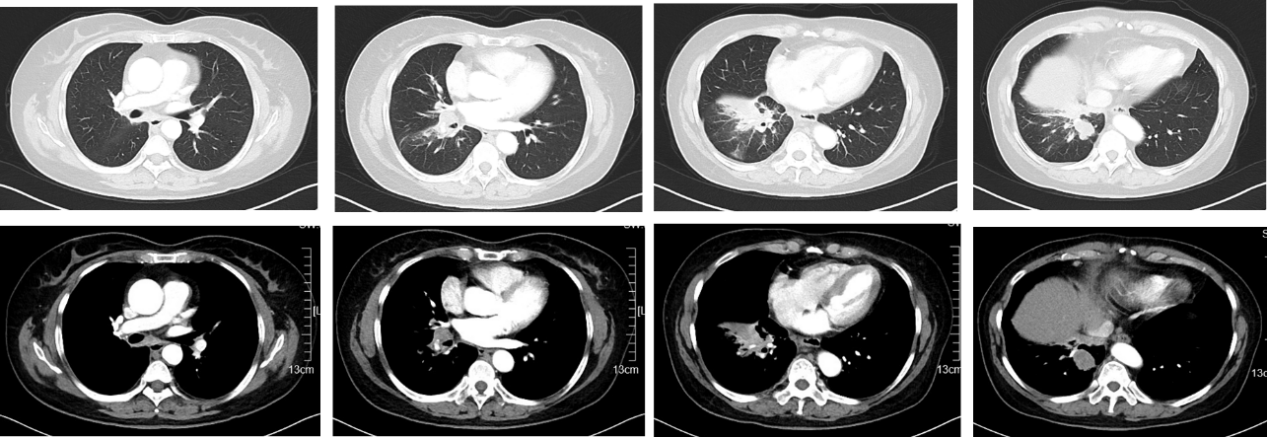

2023年2月,查胸部增强CT(图1)示:右肺下叶病变,伴部分肺实变,右侧肺门及纵膈内多发增大淋巴结,双肺多发磨玻璃结节。全身骨ECT(2022-03-03,图2)示:左6前肋骨代谢增高;T5、L5椎体骨代谢增高,结合病史提示骨转移。腹部CT、头颅MRI未见明显转移。

诊断方面,患者查胸部增强CT提示右肺下叶病变;全身骨ECT显示骨代谢增高,提示骨转移;腹部CT、头颅MRI未见明显转移。CT引导下经皮肺穿刺活检、超声支气管镜明确为肺腺癌,最终确诊为右肺腺癌(c-T2N2M1),基因检测提示TP53突变。